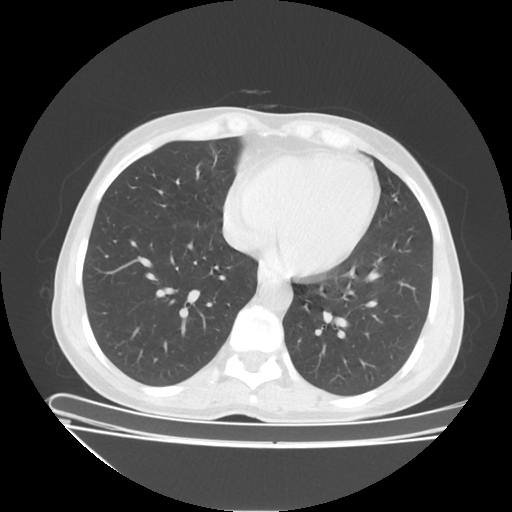

Original NATIVE CT scan (input)

No window - Raw intensity values

Lung window (WL -600, WW 1500 β†’ Low βˆ’1350, High +150)

Mediastinum window (WL 40, WW 400 β†’ Low βˆ’160, High +240)